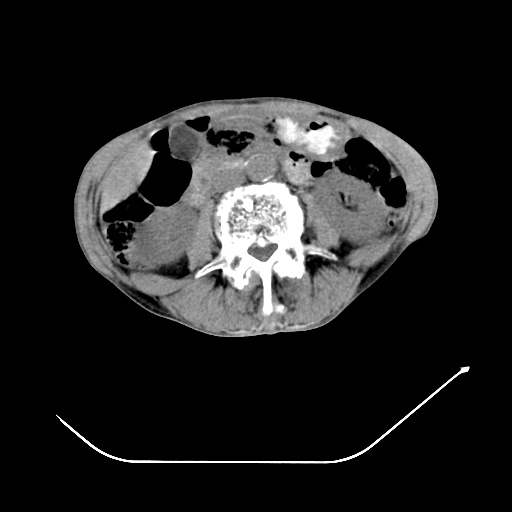

以下是引用zsl6918在2008-8-25 21:55:00的发言:[br]符合右肺周围性肺癌并肺内转移,左肺结核球。双肺肺气肿。腰椎附件转移。

以下是引用随光逐影在2008-8-25 22:03:00的发言:[br]1)考虑右肺下叶周围性肺癌并肺内转移,腰椎附件转移。2)左上肺结核(结核球形成)。3)双肺肺气肿(多发肺大泡形成)。4)双肺门区及纵隔内多发淋巴结钙化。